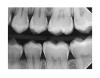

(18.) Radiograph of teenage patient showing maxillary left first premolar, which will be scheduled for disto-occlusal restoration, and all other proximal sites that will be treated with dental pick applied SDF. Additional application of SDF planned for 3 months and new bitewing films to be recorded in 6 months.

Figure 18